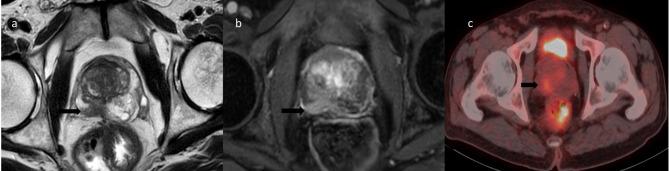

While 18 F-FDG-PET/CT is useful for characterizing a variety of cancers, it is not advised for prostate cancer that is localized. This work investigates the use of mpMRI to describe incidental 18 F-FDG uptake in the prostate.mpMRI included T2-weighted (T2W), dynamic contrast enhancement (DCE), and apparent diffusion coefficient (ADC) sequences. Patients were classified according to PI-RADS (Prostate Imaging Reporting and Data System) version 2.1 by an experienced uroradiologist, and 18 F-FDG-PET was evaluated to determine whether the area of involvement on CT had a counterpart in mpMRI. A biopsy was performed on 30 of the 92 patients. These patients' maximum standardized uptake values (SUVmax) 6 < and ≥ 6, PS(PSA) density 0.15 < and ≥ 0.15, PSA level, uptake pattern (focal involvement/diffuse involvement), and PI-RADS scores were compared. P < .05 was considered statistically significant. Logistic regression was used to analyze PI-RADS score groups age, PSA, PSA density and SUVmax.

In the study, 92 patients with incidental 18 F-FDG-PET/CT prostate uptake were examined. Median age was 66, PSA median was 3.6 ng/ml (range: 0-3198 ng/ml). Notably, in 70.6% of cases, PET/CT uptake didn't correlate with mp-MRI findings. Among PI-RADS 3-4-5 patients (29.3%), there was a correlation. Biopsies in 30 patients revealed 43.3% benign, 56.7% malignant. Significant differences between benign and malignant cases were observed in PSA density, PI-RADS scores, and PSA levels (p < .05), while SUVmax and uptake pattern were not significant. In multivariate logistic regression analysis, PI-RADS score groups were found to be independent risk factors for predicting malignancy.